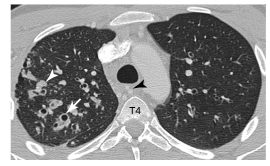

Fig. 92.2. Scanner thoracique avec injection de produit de contraste iodé réalisé devant des hémoptysies dans un contexte de mucoviscidose.

Lésions lobaires supérieures droites associant des bronchectasies à paroi épaisse (flèche), des bronchocèles (tête de flèche) et des micronodules de surinfection.

Source : CERF, CNEBMN, 2022.